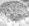

La biopsia de piel de los pacientes con CADASIL muestra en las microfotografías electrónicas una deformación de las células musculares lisas con infiltraciones de un material granuloso osmiofílico (GOM) lo que tiene un valor diagnóstico significativo